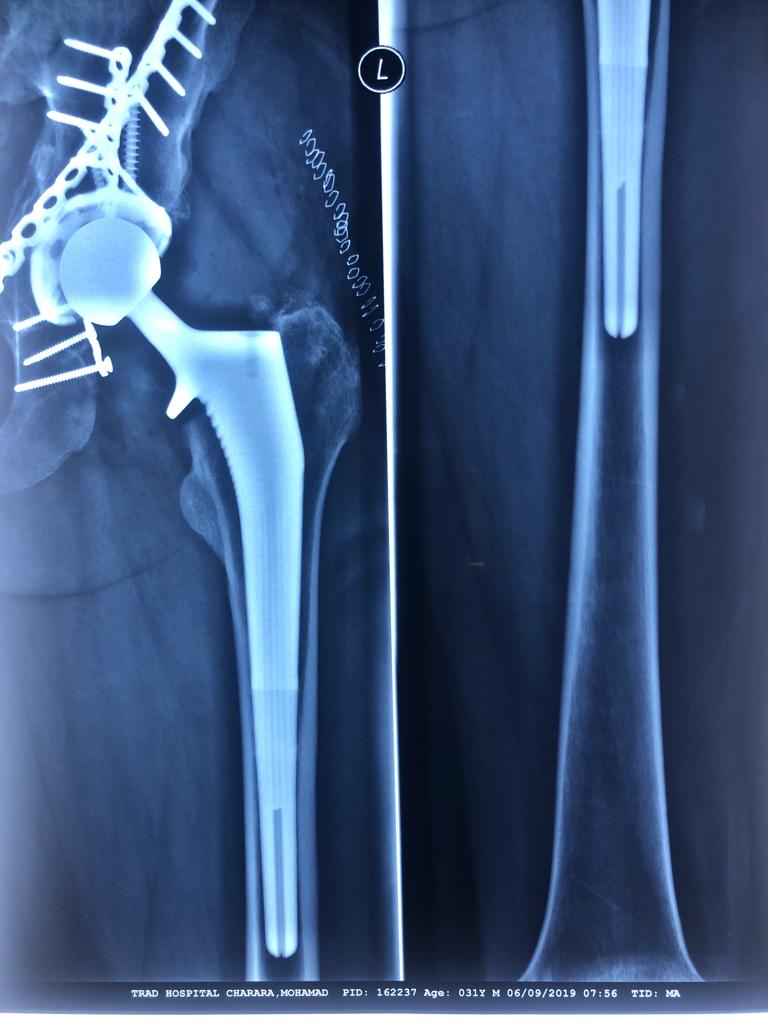

Revision Total Hip Arthroplasty Femoral Stem